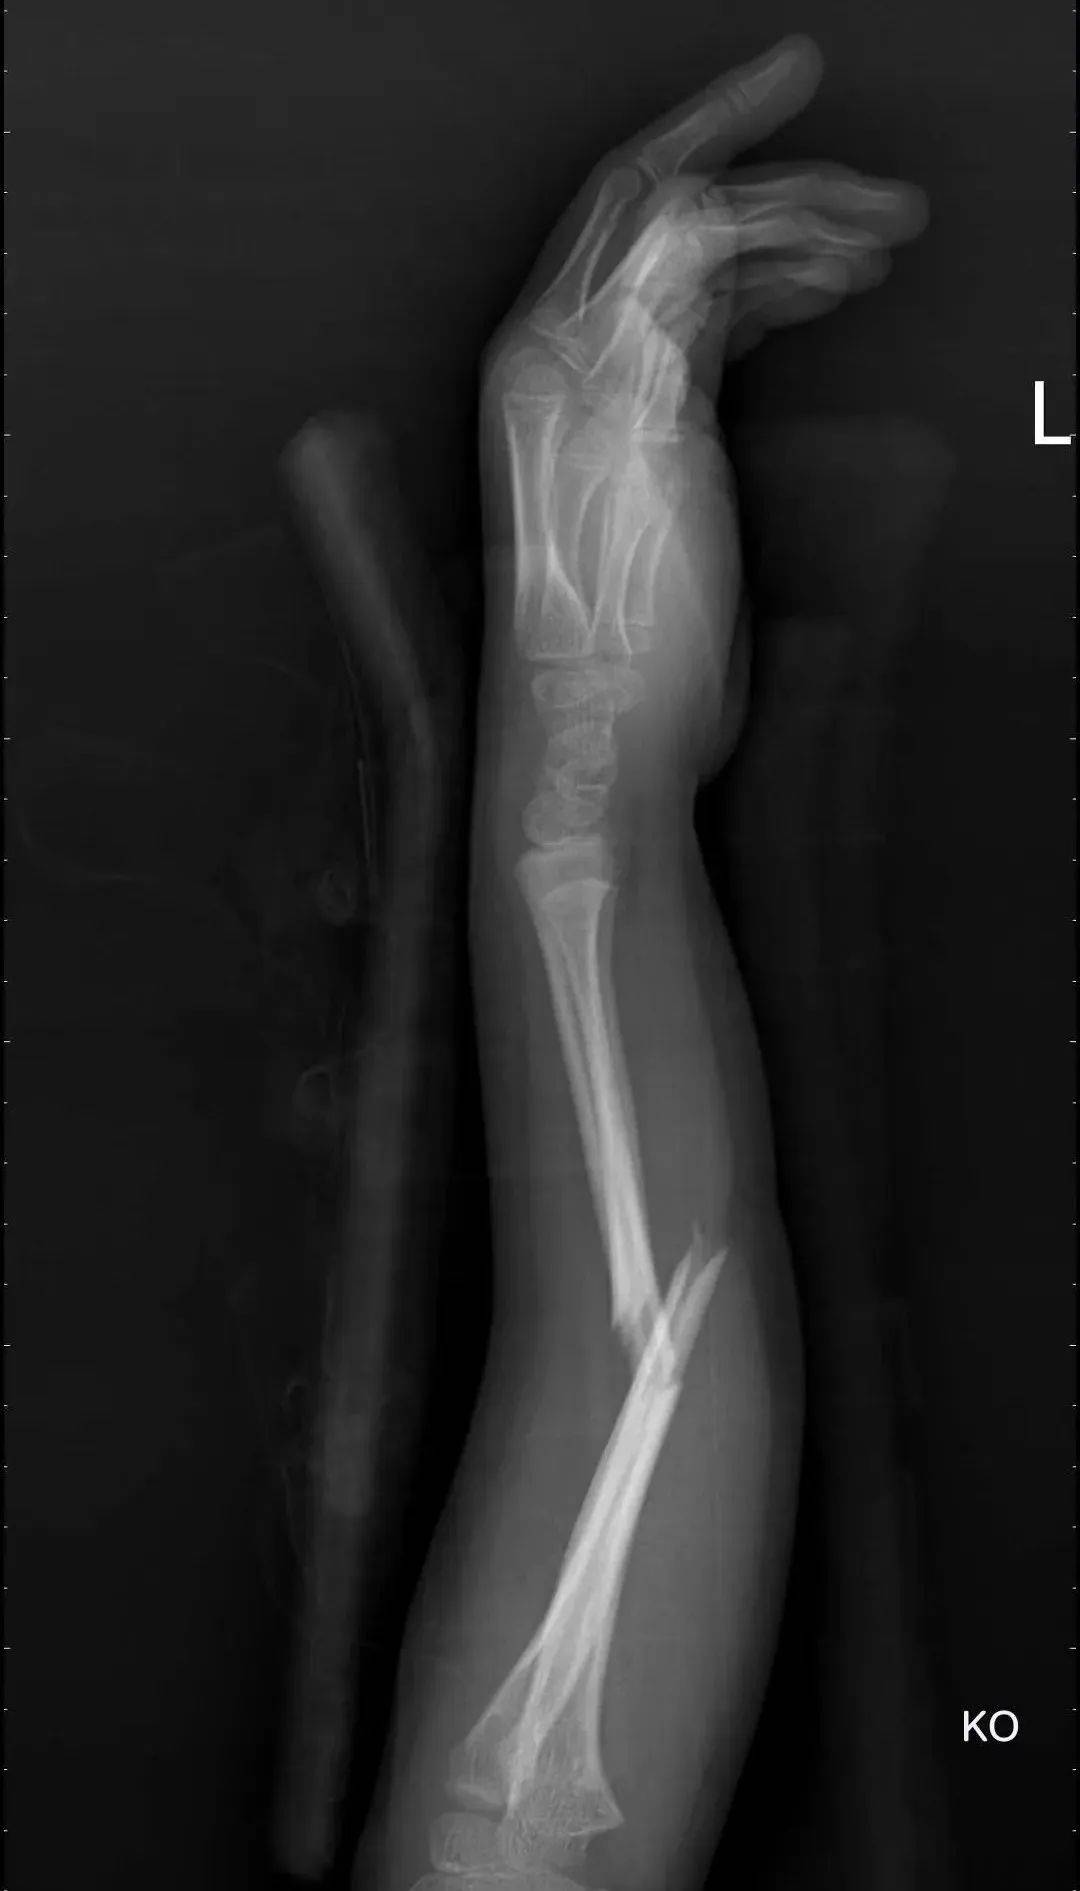

今年的6月7日我院手足外科接诊了一位7岁的小朋友,他的受伤机制是从高处坠落导致的尺桡骨中段骨折,到我这后家属也是优先考虑手法复位,保守治疗,我也尽我所能的予以复位,石膏外固定,复查DR片提示:桡骨基本达到解剖复位,尺骨达到功能复位,但因尺桡骨双折导致折端不稳,很容易再次错位,所以跟家属反复交代保守治疗的风险,家属也表示先考虑考虑,在后期的2次复查DR片中,虽然骨折未移位,但因天气炎热,石膏闷热、不透气,患儿非常不耐受石膏固定,家属慎重考虑后同意行弹性髓内针固定骨折。